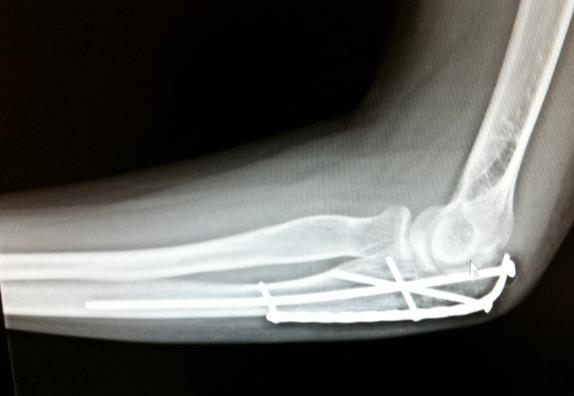

My name is Jayden Cassese and I'm a 12 year old baseball player for the TYA Tigers. In the first pre-season tournament for our big 12U season, I collided with the shortstop sliding into second base and broke off the end of the elbow bone in my left arm. This was the big year for Little League and we had the famous Cooperstown Tournament coming up in July, playing against 100 teams from around the country. I was devastated at the idea of missing that after years of building up to it.

Luckily for us, we knew friends of Dr. Green, and a fellow surgeon at HSS, and both of them strongly recommended we use Dr. Green to repair the elbow. 2 days later I was getting operated on at HSS in Manhattan, and the entire process was handled very well by Dr. Green and his entire staff. After putting 2 pins in my elbow and allowing it several months to heal, while doing PT at HSS along the way, I was able to get back on the field just in time for my big tournament. I came back stronger than ever and hit 2 home runs in one game my first weekend back, then 3 home runs the next week while at Cooperstown! Thank you Dr. Green and team for helping me make it to Cooperstown and beyond.